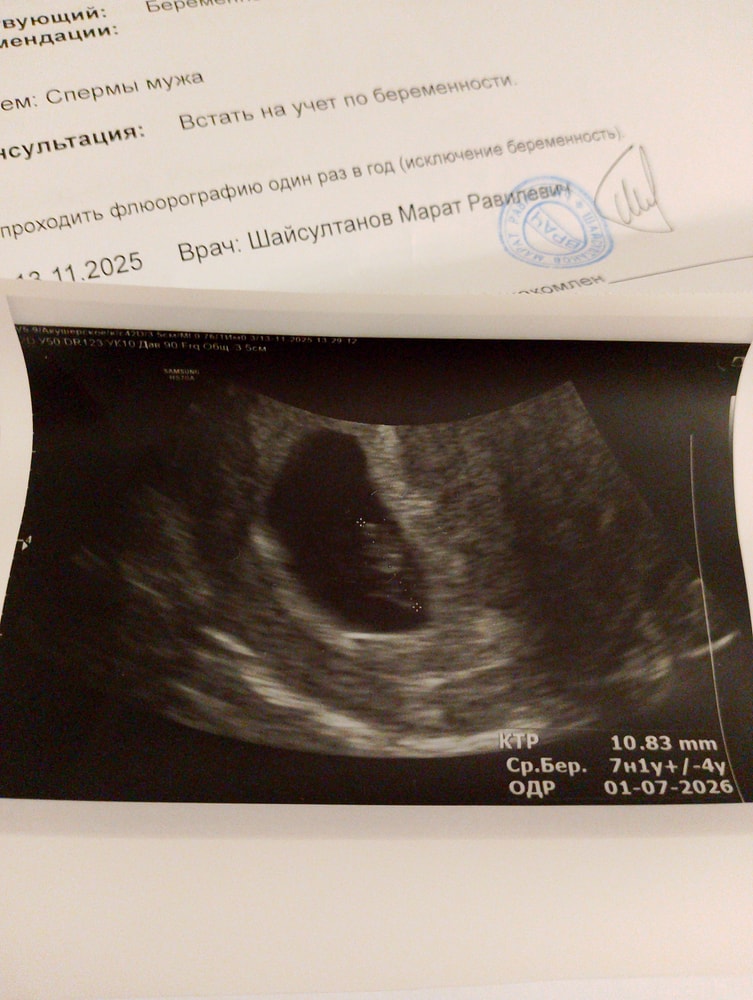

По месячным срок больше по ктр меньше, это не страшно? По переносу эмбриона вообще другой срок, перенос был 12 октября

У кого какой ктр был на таком сроке?

Божечки😇сердечко 134 удара, беременность 7 недель 1 день

Малыш наш мы тебя ждём очень🙏

Плодное яйцо 11,38

Желточный мешок есть сказали а где оно?